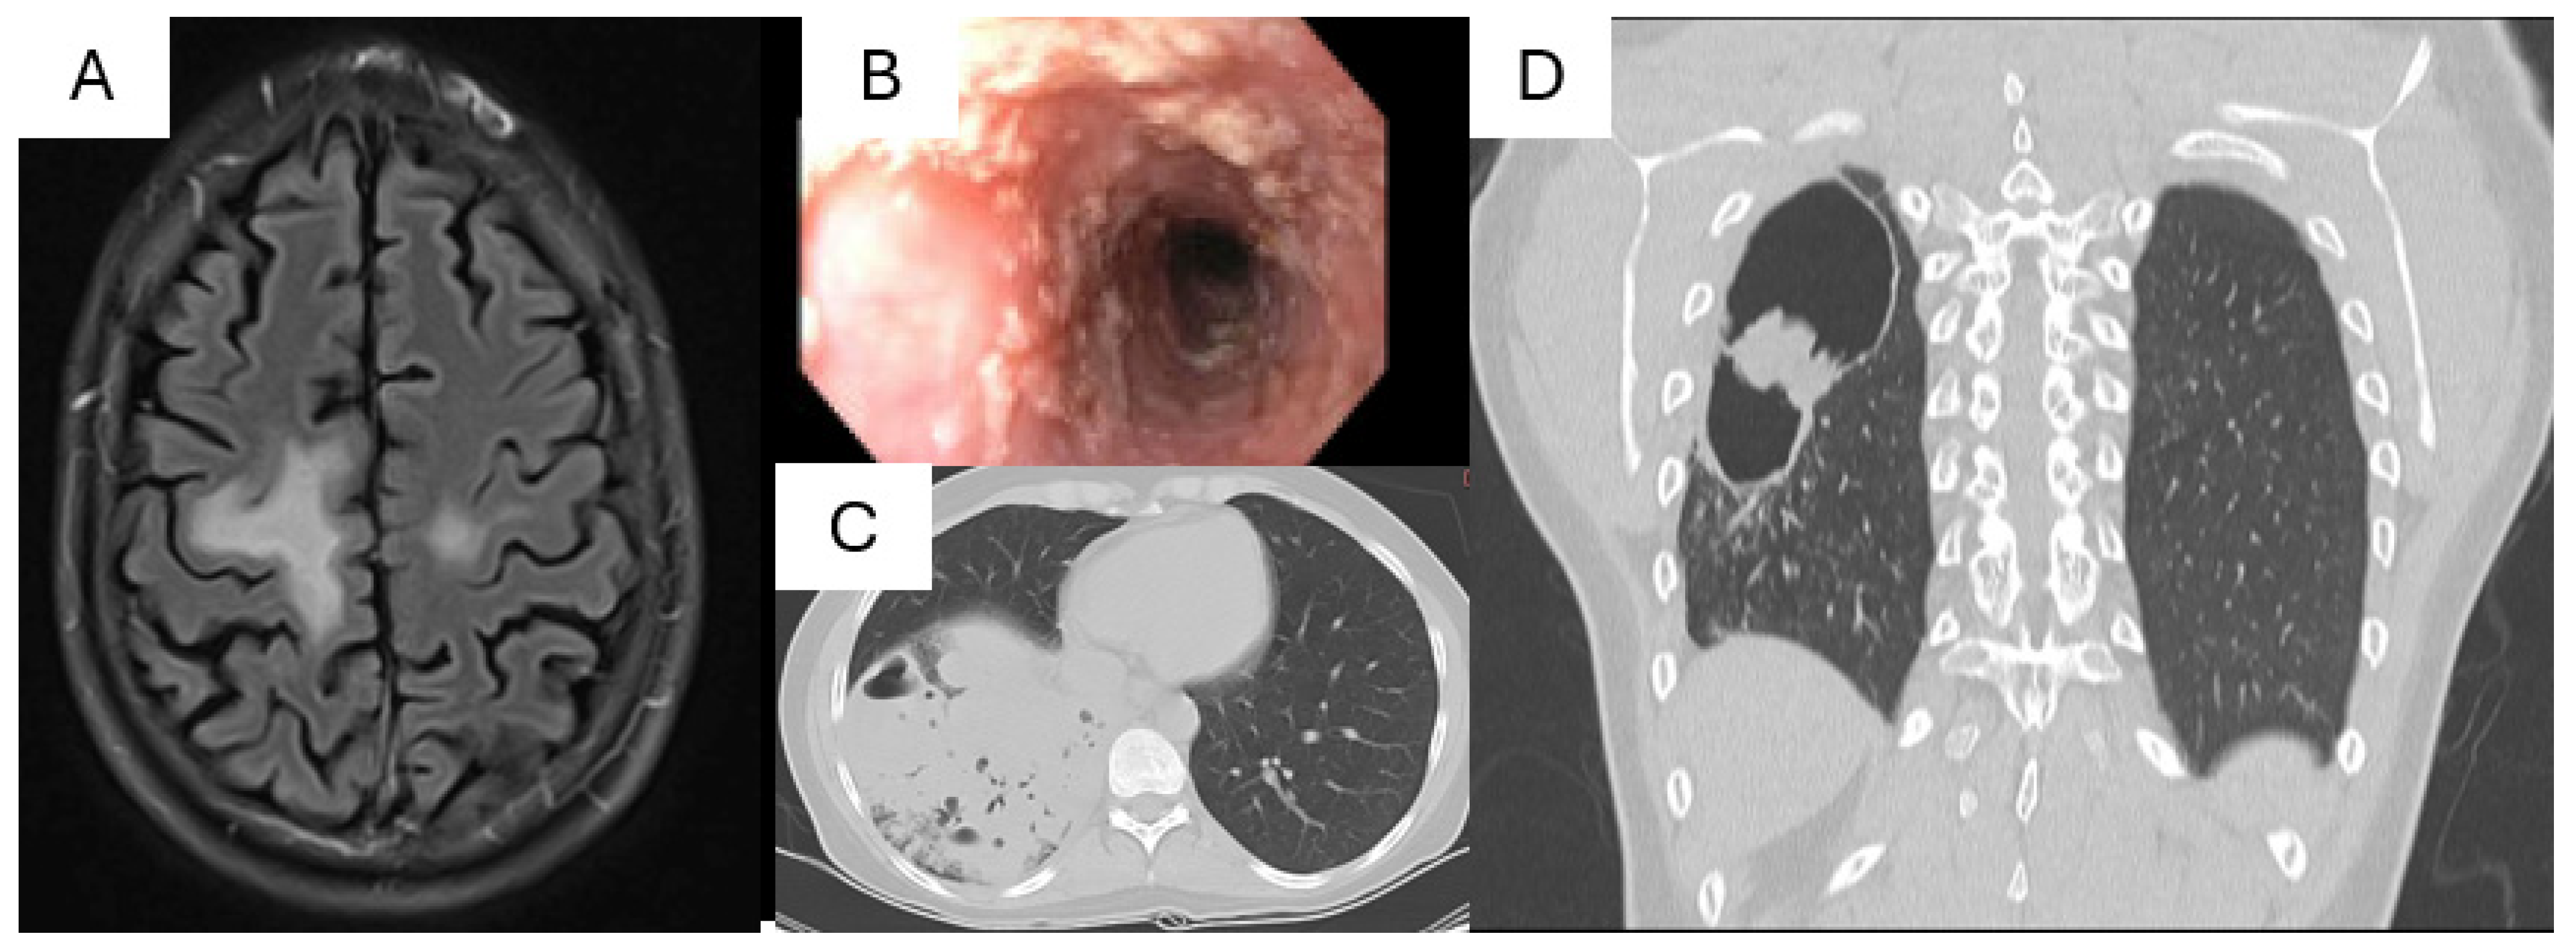

- Zerbe, C.S.; Marciano, B.E.; Katial, R.K.; Santos, C.B.; Adamo, N.; Hsu, A.P.; Hanks, M.E.; Darnell, D.N.; Quezado, M.M.; Frein, C.; et al. Progressive Multifocal Leukoencephalopathy in Primary Immune Deficiencies: Stat1 Gain of Function and Review of the Literature. Clin. Infect. Dis. 2016, 62, 986–994. [Google Scholar] [CrossRef]